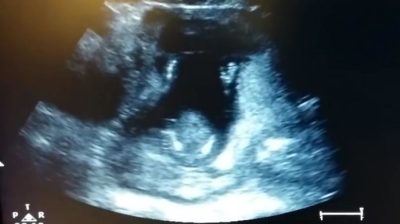

ทางการแพทย์สำหรับซาวด์, ตั้งครรภ์ 14 สัปดาห์และสามีของเธอสังเกตเห็นว่าลูกของพวกเขาดูเหมือนจะจับมือของเขาเป็นจังหวะ, เช่นตีปรบมือ. ขณะที่พวกเขาถูกบันทึกเหตุการณ์บนวิดีโอ, จึงตัดสินใจร้องเพลงจังหวะของเด็ก.